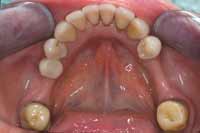

Figure 1

The patient was unhappy with the esthetics of her smile. Note the uphill cant to the left.

Figure 2

Several occlusal flags included crowded anteriors and abfractions.

Figure 4 Pretreatment upper study model. Crowded maxillary anteriors and “V”-shaped arch form.

Figure 5 Pretreatment lower study model. Crowded mandibular anteriors, “V“-shaped arch form, and blocked out tooth No. 22.